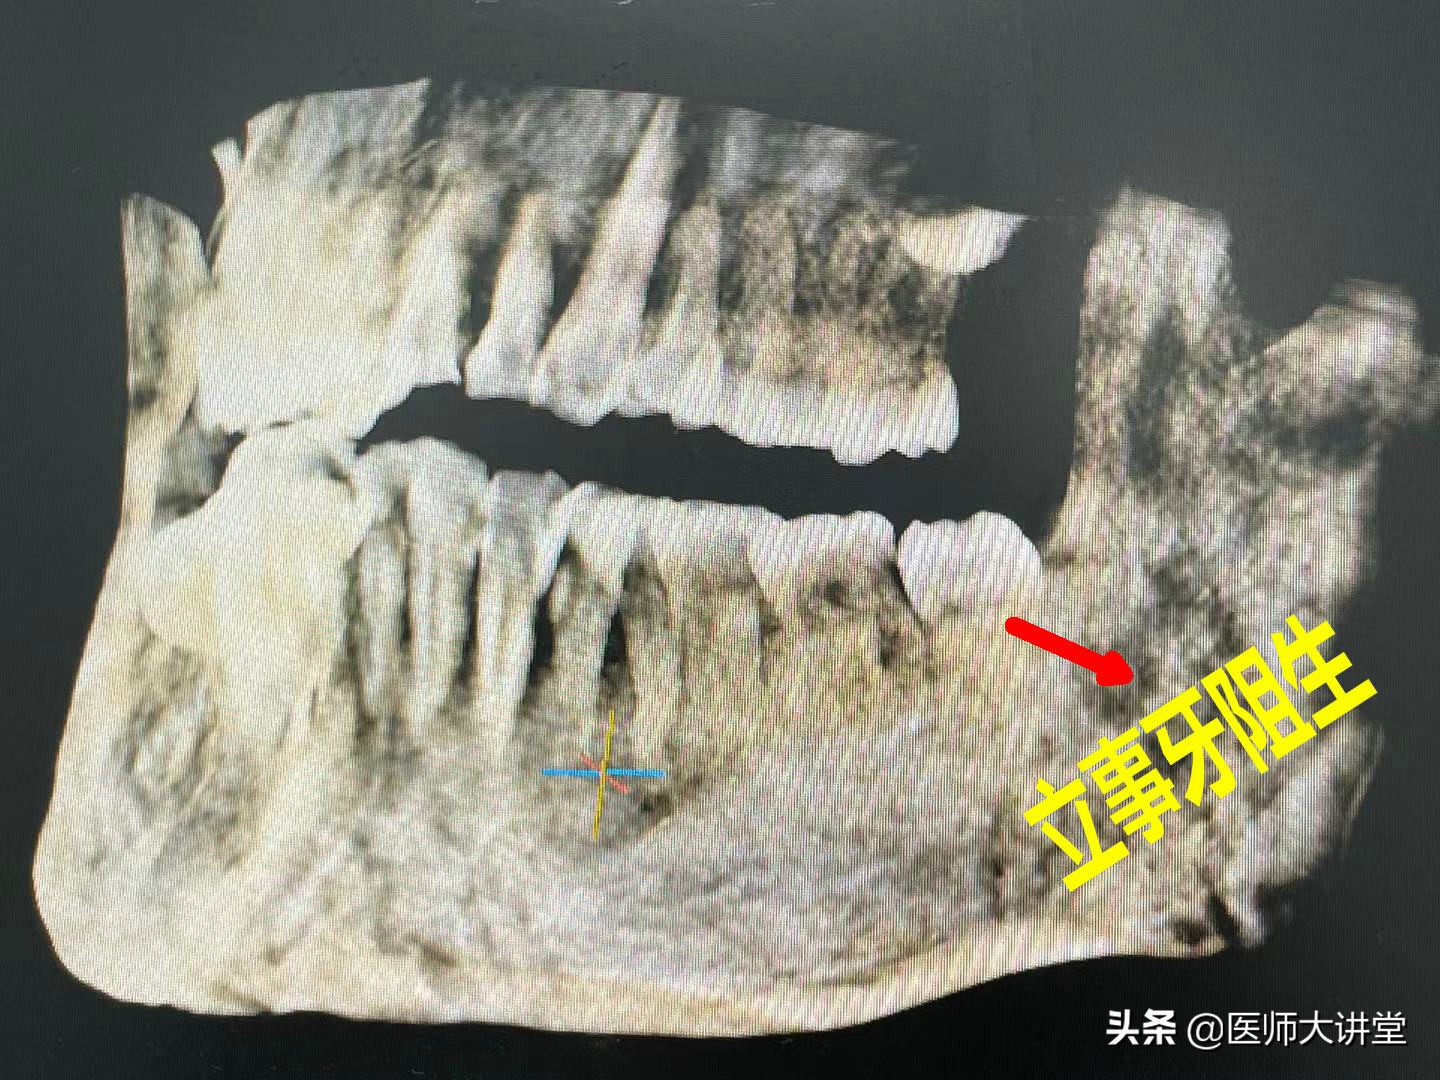

口腔检查:口腔卫生一般,松动1度,牙龈无红肿 CBCT检查:左下立事牙阻生,

进行CBCT检查 第二次拍CT检查 初步诊断:非腐败型干槽症

第一次拍CT 拔牙窝内发现有不明物体。智齿拔的部位有一个洞(牙槽窝),口腔检查后发现一块豆牙皮把整个牙槽窝口封住。还有其他一些食物残渣。进一步查看里面碘仿药丸没有吸收。发现牙槽窝没有吸收愈合,呈空虚状。